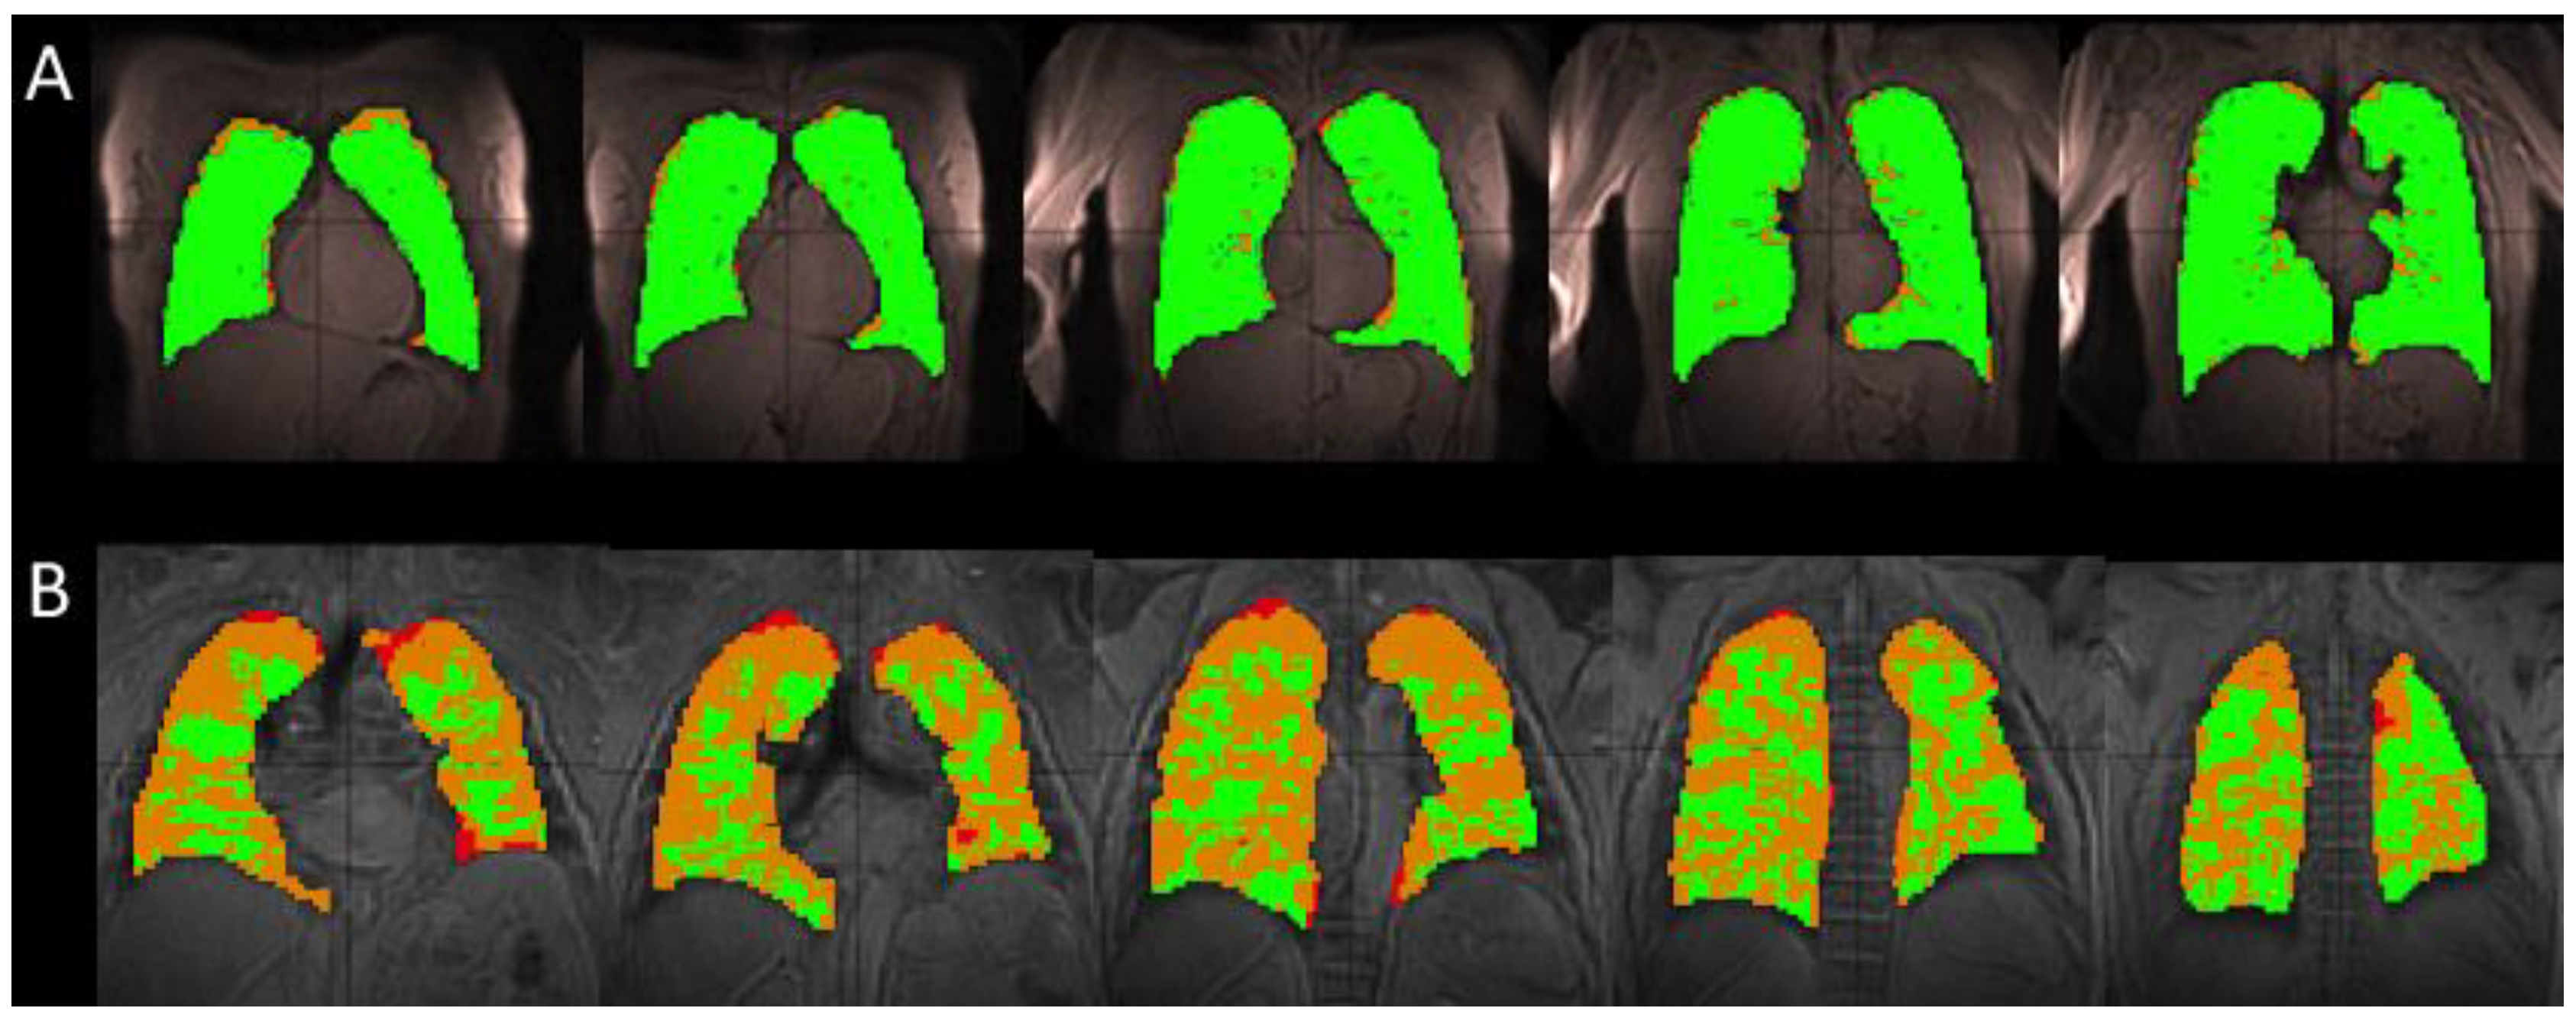

Figure 1.

A comparison of the segmented ventilation images for a single healthy (H2) (A) and IPF (I2) subject (B). The healthy subject has mainly areas of normal (green) ventilation, with hypoventilation (orange) and no ventilation (red) areas located on the periphery of the lung, occupying 4.8% of the total lung volume for this particular subject. In the IPF subject, these large ventilation defects located on the periphery of the lung encroach toward the center of the lung, occupying 35.1% of the total lung volume. The IPF subject retained a portion of the inhaled xenon in the trachea and bronchi, resulting in the high intensity of gas in those areas (not shown). The segmentation algorithm excluded these regions to avoid overestimating the volume of the lungs and areas of ventilation.

As seen in the segmented Xe-129 ventilation MR images in Figure 1A, the lungs of healthy subjects were well ventilated and had few ventilation defects. IPF subjects had multiple ventilation defects predominantly located at the lung periphery, as seen in Figure 1B.

Subjects with IPF had significantly increased volumes of ventilation defects (VD), defined as volumes with no ventilation at all, plus volumes with hypoventilation or lower SNR, as compared with healthy subjects. Healthy subjects had 9.6 ± 7.37% VD, while IPF subjects had 34.1 ± 6.44% VD (p < 0.01; Figure 1). Additionally, healthy subjects had an average FVC of 4.6 ± 0.91 L and total lung volume calculated from the ventilation images equal to 4.1 ± 0.56 L. IPF subjects had lower spirometry FVC values, 2.4 ± 0.87 L, compared with the total volume calculated from the ventilation images, 2.6 ± 0.70 L. In both groups, spirometry measurements had higher standard deviations.